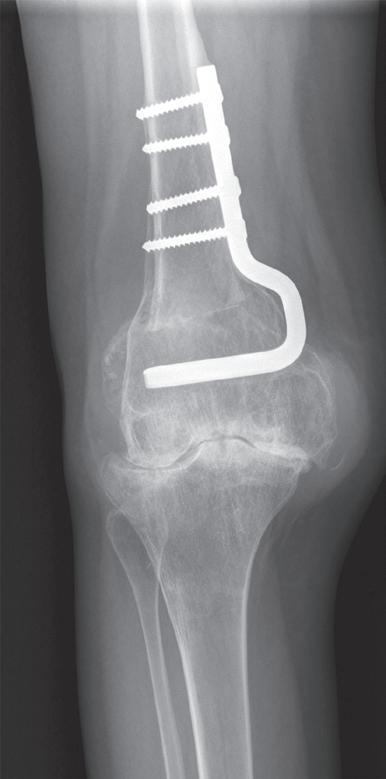

Osteotomie má za cíl korekci kloubní osy se změnou zátěžových oblastí kloubu. Operace obnoví osu končetiny a odlehčí tlak na poškozenou oblast kloubu a zmírní tak subjektivní obtíže nemocného. Příznivý výsledek obvykle přetrvává několik let. Dle poruchy osy rozlišujeme osteomie valgizační (korekce genu varum) a varizační (korekce genu valgum). V praxi se provádí klínovitá osteotomie s vytětím kostního klínu, sesazením obou fragmentů a fixací osteosyntézou (tzv. closed wedge osteotomie, obr. 19.5). Druhou možností je provedení jednoduché osteotomie s rozevřením obou fragmentů v klínovitém tvaru a fixace osteosyntézou (tzv. open wedge osteotomie, obr. 19.6). Dále podle anatomické lokality osteotomie rozlišujeme osteotomie distálního femuru (obr. 19.7) nebo proximální tibie. Artrodéza (ztužení kloubu) se primárně používá ve výjimečných případech (obr. 19.8). Je však možným řešením zejména po selhání aloplastiky, pokud není možná implantace nové náhrady. Vzhledem k faktu, že ztužení kloubu probíhá obvykle v terénu rozsáhlých kostních ztrát, používá se v poslední době ztužení kloubu pomocí implantátů – tzv. fúze kolenního kloubu (obr. 19.9). Nejde tedy v pravém slova smyslu o klasickou artrodézu – tedy kompletní primární kostní srůst femuru a tibie.

Obr. 19.7: Příklad varizační osteotomie distálního femuru pro valgózní deformitu kolenního kloubu. Provádí se vytětím kostního klínu na mediální straně femuru, korekcí osy a fixací pomocí osteosyntézy. Snímek pacientky po osteotomii v dětství s postupným rozvojem artrotických změn.